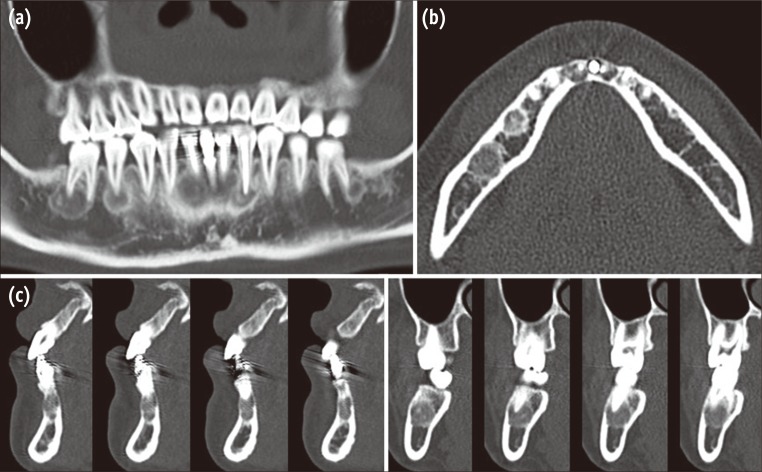

Figure 5

Radiographic examinations performed in 2011. A panoramic reconstructed image of cone-beam computed tomography (CBCT) obtained in September, 2011 (21 months after the biopsy).

The patient visited the hospital without an appointment 21 months after the biopsy because of discomfort in the mandibular anterior vestibule. Her chief complaint was pain on palpation, which had started 2 days prior to her visit. No signs of infection were detected. Cone-beam CT (CBCT, Pax-Zenith3D, Vatech, Hwaseong, Korea, 104 Kvp, 5.5 mA) radiograph was taken to assess any changes in lesion size and development (Figure 5). Based on CBCT views, the apical lesions of madibular anterior teeth and the implant appeared to become more radiopaque. The patient was requested to return if she exhibited any signs of fever, swelling or pain. She did not experience any discomfort after the emergency visit. The patient was instructed to maintain annual routine check-ups.

A biopsy is the only definitive method for distinguishing COD from other bony lesions. However, a surgical biopsy is rarely performed. Conversely, a biopsy is recommended when the diagnosis is unclear.16,17 A biopsy of the lesion on the anterior teeth was performed in this case to confirm the diagnosis of COD and to eliminate the possibility of secondary infection due to the perforated cortical bone, since the patient had experienced slight discomfort during palpation. The texture and features of the removed specimen were consistent with those of a case described previously, in which multiple gritty fragments were obtained.18 The biopsy lesion revealed multiple bony or cementum like material and fibrous connective tissue, which was the typical appearance of COD from previous findings.10,18 Unlike cemento-ossifying fibroma, fibrous dysplasia of the jaw is a non-demarcated lesion, and it is self-limiting. However, in many instances, after the active phase of the lesion has passed, the affected bone never returns to normal, either radiographically and histologically.2 Thus, an old area of fibrous dysplasia is sometimes explored surgically, and the tissue shows a rather characteristic appearance which is sometimes referred to as an osteoid keloid.19 This was consistent with our finding that a slightly radiolucent area of the madibular right lateral incisor (#42) remained in the 21-month CBCT images (Figure 5).

To manage COD, no treatment is necessary; however, periodic clinical and radiographic follow-up is recommended.9 In an asymptomatic case, regular routine check-ups are recommended, with panoramic radiographs. Because lower anterior lesions are often blurred in a panoramic view, additional periapical radiographs of the mandibular anterior teeth can be obtained. CT may be valuable for the assessment of newly developed signs and symptoms.3,20 In this case, CT was performed when the patient was referred to the specialist. A meticulous review of the CT scans may have helped to avoid endondontic surgery. None of the lesions detected by CT showed any expansion of the cortical plates, which may have been an indication for the elimination of cyst-like lesions. According to Alsufyani and Lam, the radiographic features of COD are a bilateral occurrence, involving the anterior and posterior teeth simultaneously, with a well-defined border, a radiolucent rim and a mixed radiolucent and radiopaque structure.21 CBCT scans were repeated during the check-ups performed after the patient had expressed intermittent discomfort. Compared with CT, CBCT is associated with reduced radiation levels and provides enough information to diagnose COD lesions. However, in this case, the CBCT obtained in 21 months was not considered the ideal approach due to the unnecessary exposure to radiation. Instead, close follow-up examinations, without further panoramic radiography may be recommended in this situation.